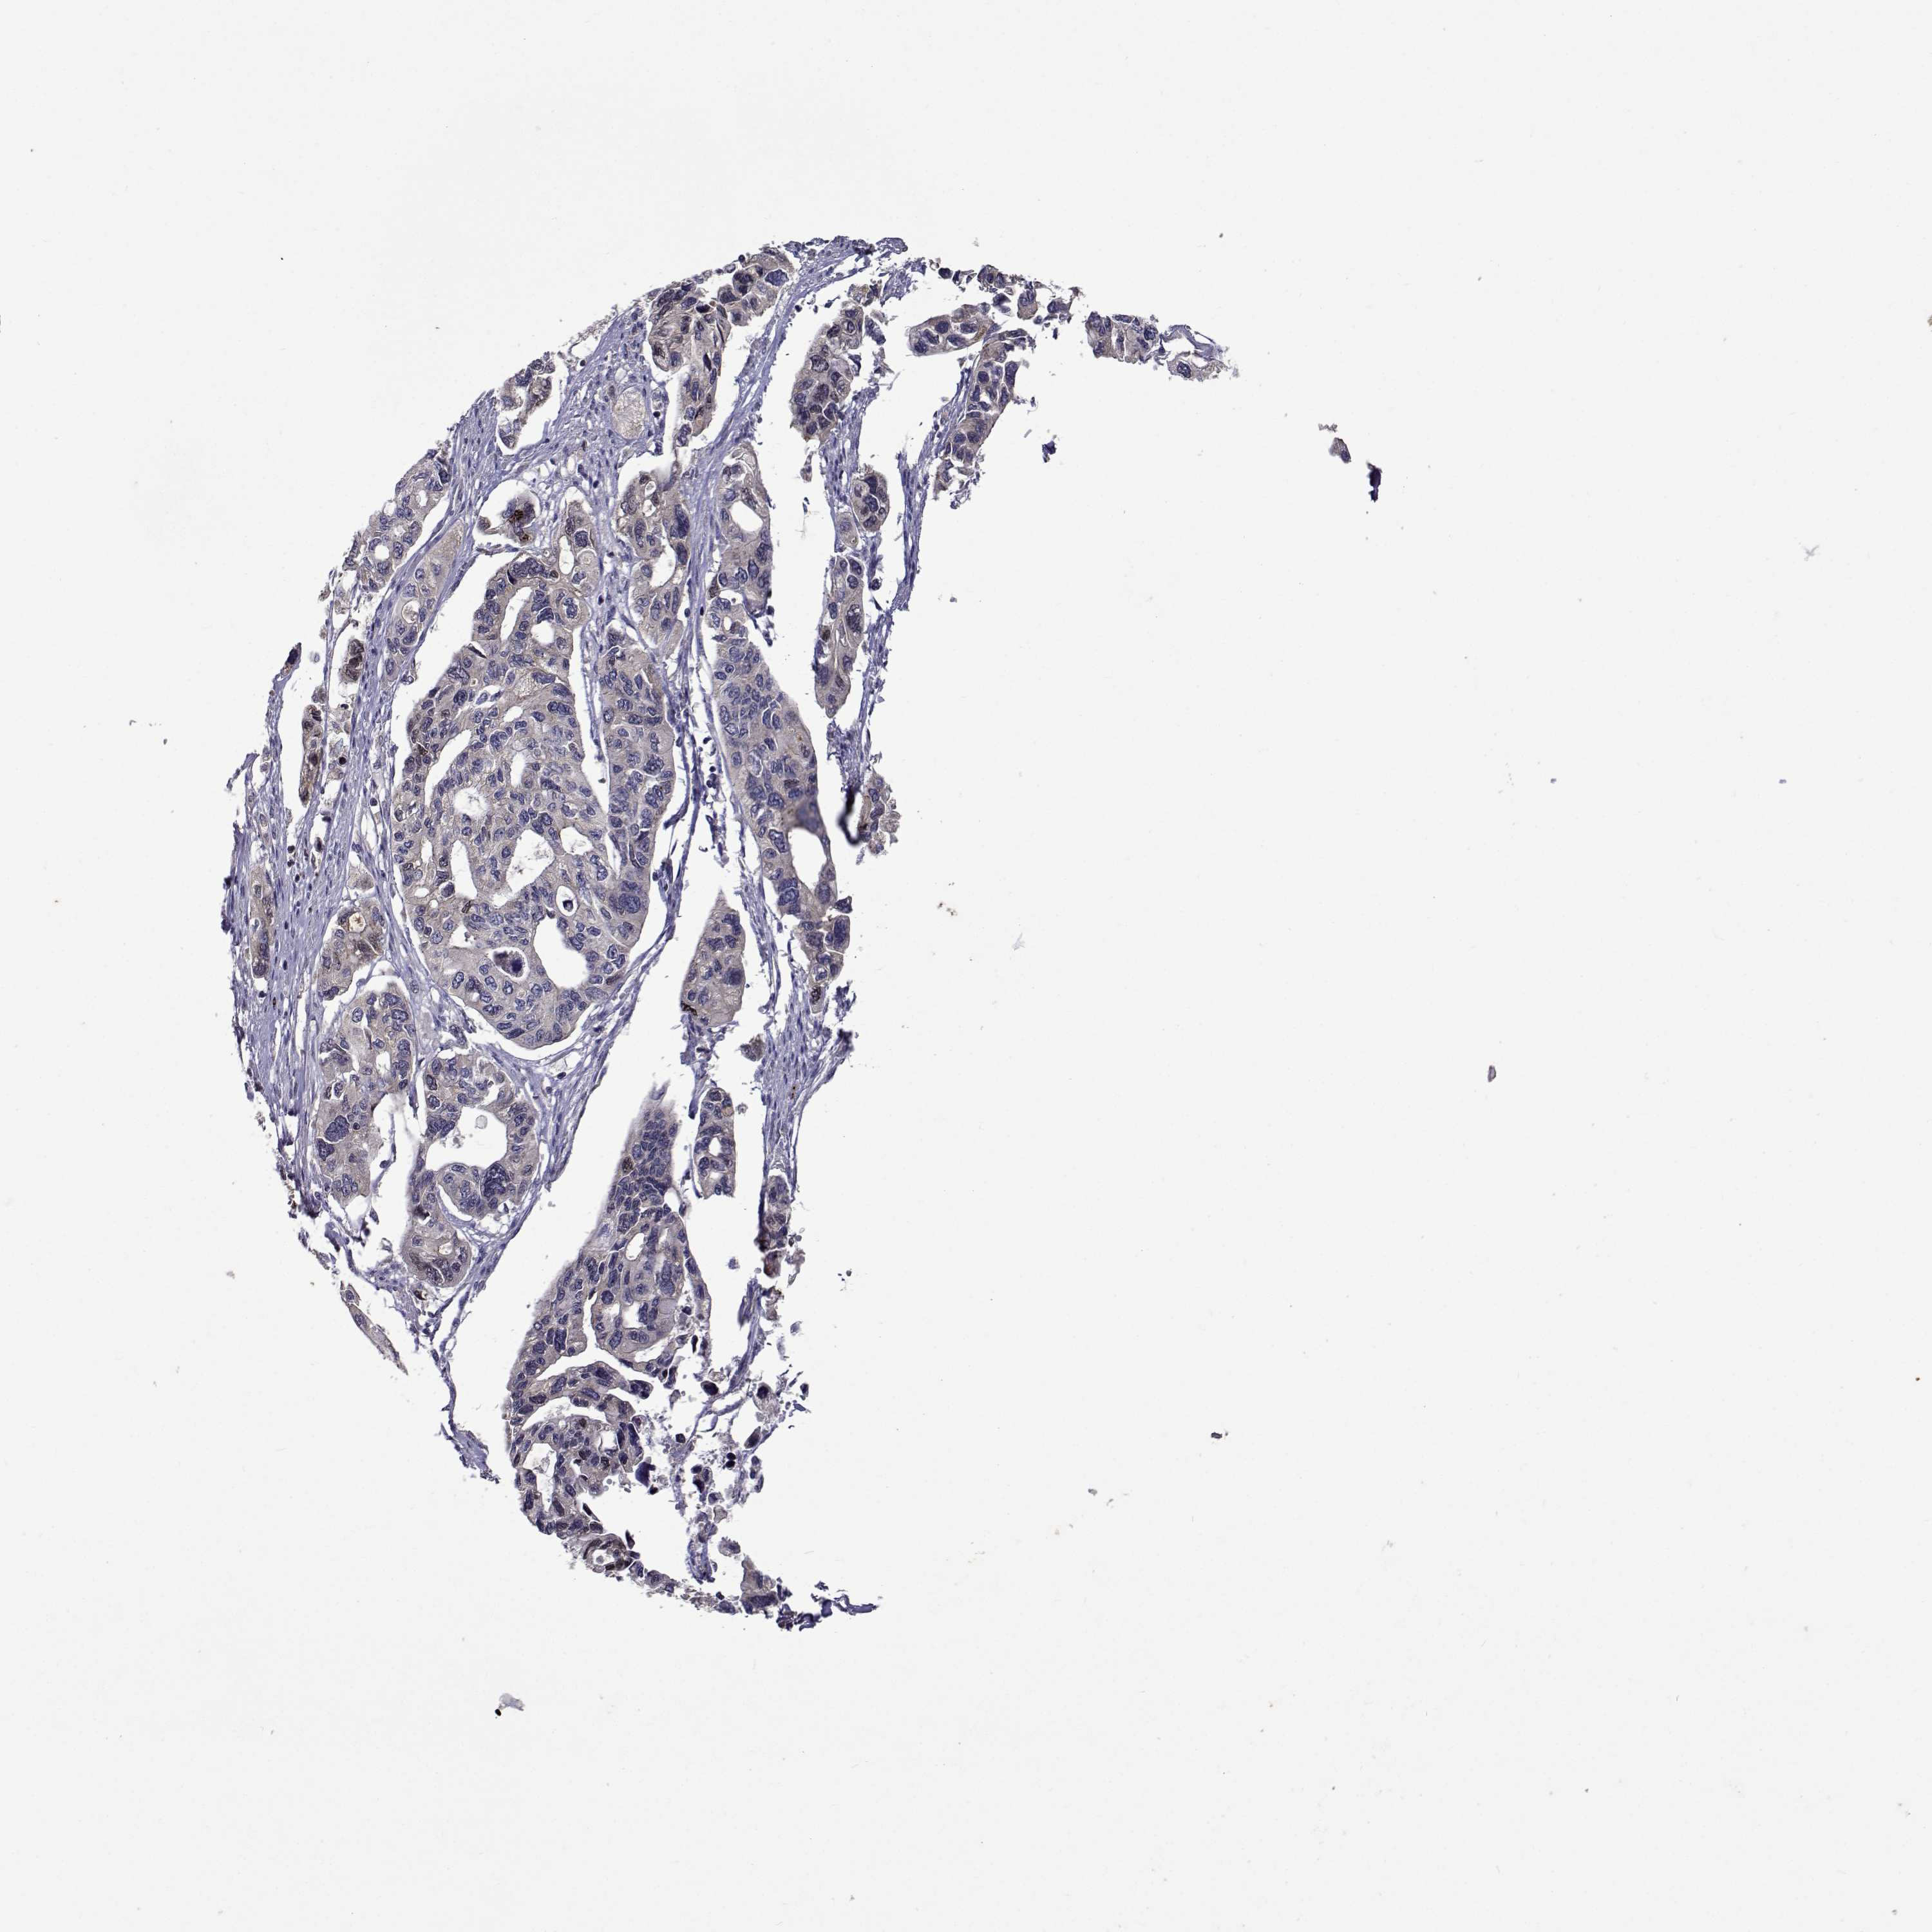

PANCREATIC CANCER - Protein expressioni

A mouse-over function shows sample information and annotation data. Click on an image to view it in a full screen mode. Samples can be filtered based on level of antibody staining by selecting one or several of the following categories: high, medium, low and not detected. The assay and annotation is described here.

Note that samples used for immunohistochemistry by the Human Protein Atlas do not correspond to samples in the TCGA dataset.

Antibody stainingi

Antibody staining in the annotated cell types in the current human tissue is reported as not detected, low, medium, or high, based on conventional immunohistochemistry profiling in selected tissues. This score is based on the combination of the staining intensity and fraction of stained cells.

Each image is clickable and will lead to virtual microscopy that enables deeper exploration of all samples and also displays staining intensity scores, fraction scores and subcellular localization as well as patient and tissue information for each sample.

Antibody HPA051181

Antibody HPA061454

Antibody CAB069406

Staining

High

Medium

Low

Not detected

Intensity

Strong

Moderate

Weak

Negative

Quantity

>75%

75%-25%

<25%

None

Location

Nuclear

Cytoplasmic/membranous

Cytoplasmic/membranous,nuclear

Adenocarcinoma, NOS